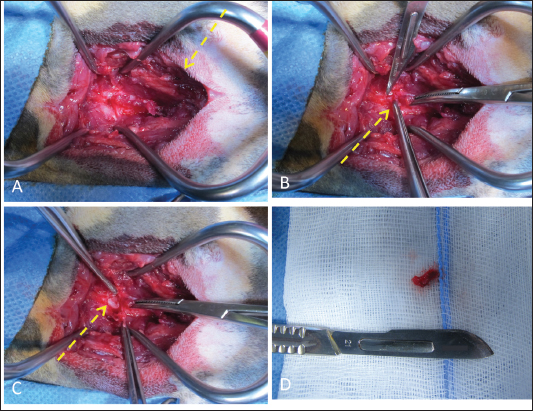

On arrival, venous blood gas analysis revealed mild respiratory acidosis and mild hyperlactatemia (Table 1). The complete blood count revealed moderate thrombocytopenia and neutrophilic leukocytosis (Table 2). Biochemical analysis showed elevated liver and muscular enzyme levels and increased serum amyloid A levels (Table 2). Hypofibrinogenemia (1.36 g/l) with unremarkable coagulation time was evident. All abnormalities were consistent with the traumatic event suspected. Thoracic radiographs confirmed the presence of severe subcutaneous emphysema, associated with moderate pneumomediastinum and mild pneumothorax (Fig. 1). Computed tomography (CT) was scheduled for the following day due to the high suspicion of tracheal injury associated with cervical compressive myelopathy. The cat was hospitalized at the intensive care unit under strict monitoring, minimizing manipulation as much as possible. Fluid therapy was set at 2 ml/kg/h IV of lactated Ringer’s solution, together with analgesic therapy with methadone at 0.1 mg/kg IV every 4 hours, and antibiotic therapy with ampicillin-sulbactam 20 mg/kg IV every 8 hours. The cat was mildly symptomatic for the pneumothorax and was therefore managed conservatively. The following day, the clinical parameters were stable, and a progressive reduction of the subcutaneous emphysema and pneumothorax was noted; therefore, the patient was sedated with 0.2 mg/kg of methadone intravenously (IV) and 2 µg/kg of dexmedetomidine IV, and then placed in a VetMouseTrapTM to avoid intubation and general anesthesia. CT scans confirmed the moderate to severe subcutaneous emphysema, pneumomediastinum, and mild pneumothorax (Fig. 2). A dorsal parietal deformation of the cervical trachea of approximately 1 cm in length was observed, causing a mild reduction in the dorsoventral tracheal diameter. There were no other airway injuries. An incomplete fracture line of the caudal margin of the C4 vertebral arch was observed. The fracture line appeared slightly left-lateralized, with a caudal bone fragment approximately 2 mm long and 5 mm wide. This fragment was dislocated into the vertebral canal, narrowing the dorsoventral diameter, with subsequent compression of the spinal cord (Fig. 3). The CT scan confirmed the suspicion of C4 vertebral fracture and tracheal rupture. Endoscopic evaluation of the upper airways and surgical treatment with a dorsal approach for spinal decompression were scheduled for the following day.

Fig. 2. Transverse CT images acquired with the cat placed in the VetMouse TrapTM. (A) Presence of gas attenuation material in the subcutis around the neck, consistent with subcutaneous emphysema. A dorsal deformation of the cervical trachea with mild reduction of the tracheal diameter is visible in the same scan (A, yellow arrow). (B) The presence of mild pneumo-mediastinum and pneumothorax is further observed, and the collapsed lung lobe is noted (B, yellow asterisk).